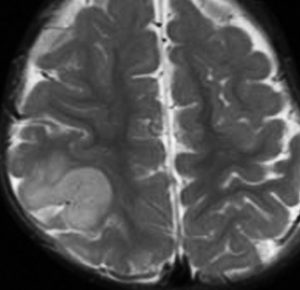

新生児期にてんかん発症した例 focal cortical dysplasia 2b

右頭頂葉の皮質異形成です。生後2週間目に両上肢を挙げるような発作を生じて難治化,1歳を超える頃には発達の遅れが目立ちました。新生児期にはMRIで描出できなかった病変が1歳になって初めて写るようになりました。手術で病変摘出 lesionectomy して投薬中断ができて,その後は普通に育ちました。